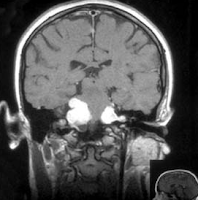

SELARES E PARASSELARES

Compreendem os tumores da

hipófise e do hipotálamo. Além das manifestações endócrinas (acromegalia, amenorreia,

diabetes insipidus, síndrome de

Cushing, etc.), são comuns as manifestações visuais (diminuição da acuidade

visual, hemianopsia bitemporal, quadrantanopsia, escotomas, atrofia ou edema de

papila). Os tumores com expansão laterosselar podem envolver os nervos

oculomotor e trigêmeo. Esses tumores podem determinar HIC.